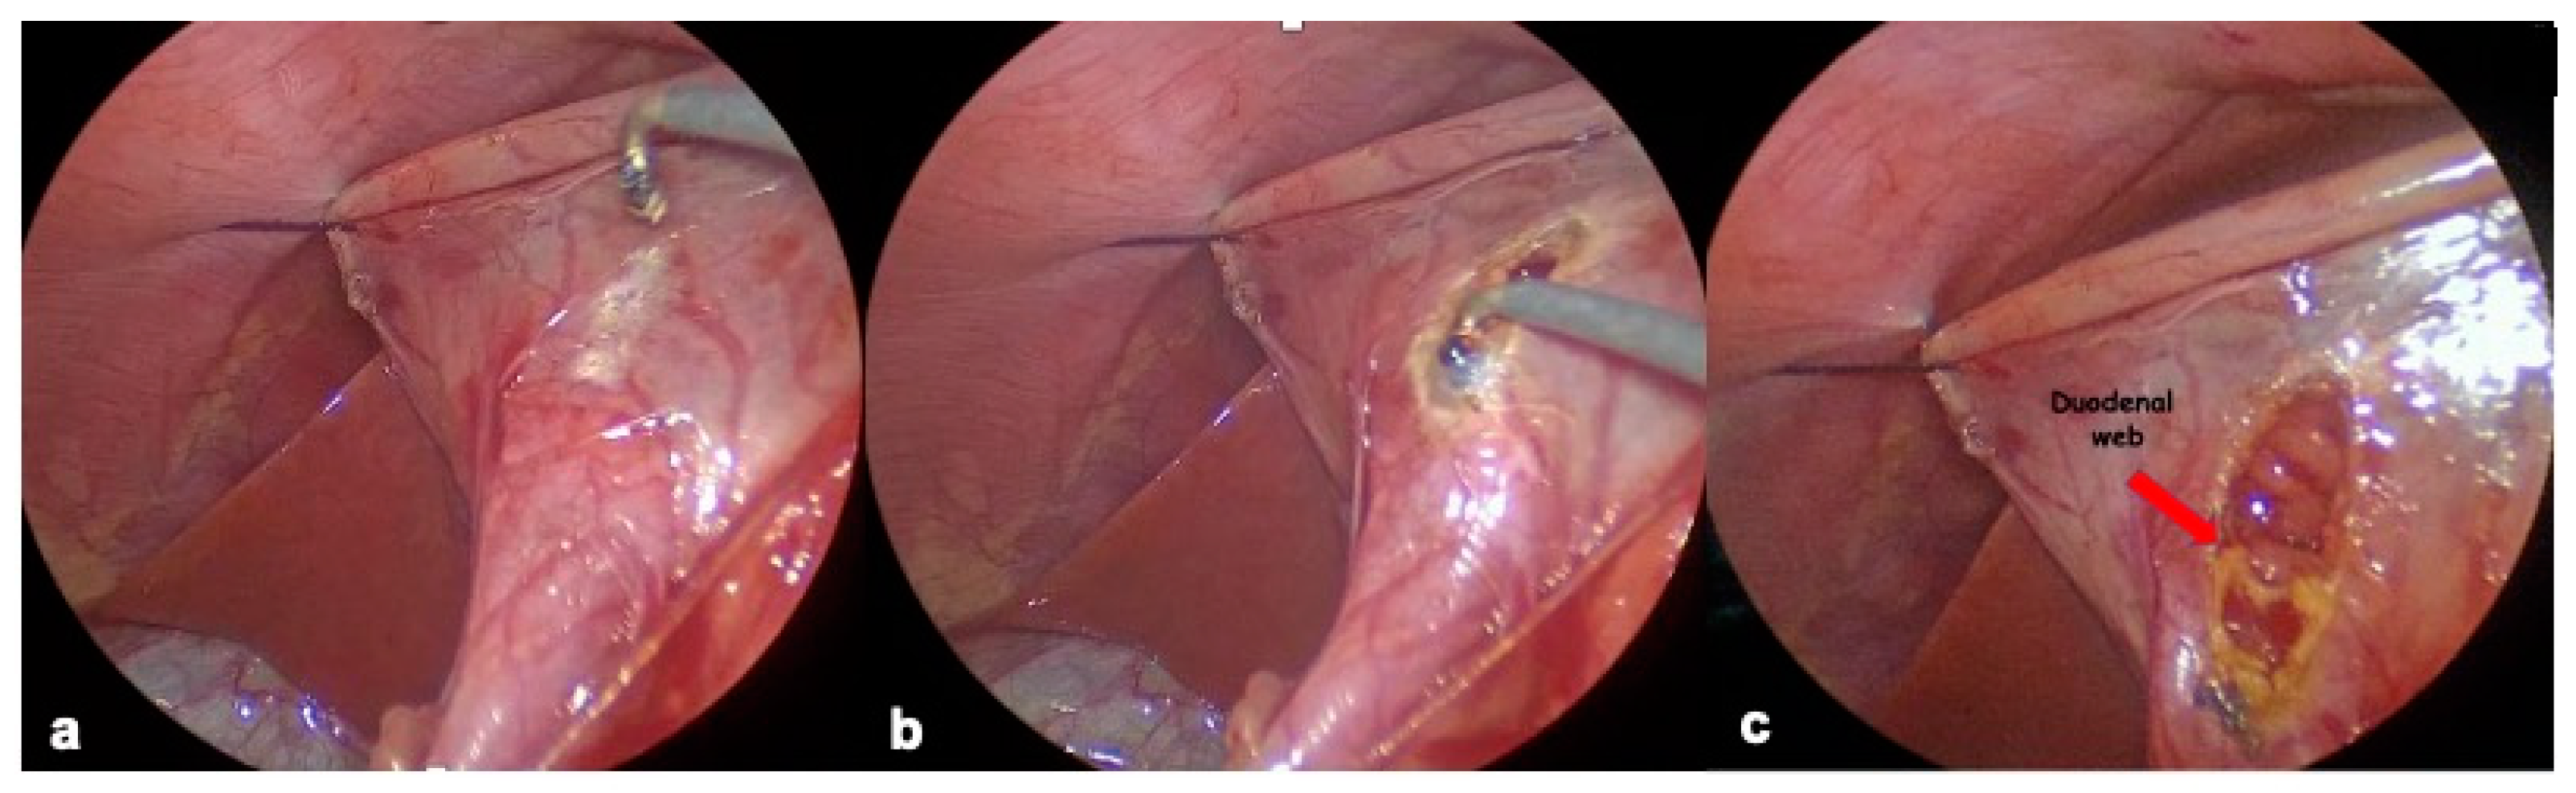

2.4.1. Endoscopic Resection

2.4.2. Laparoscopic Resection

2.4.3. Duodenal Web Localization